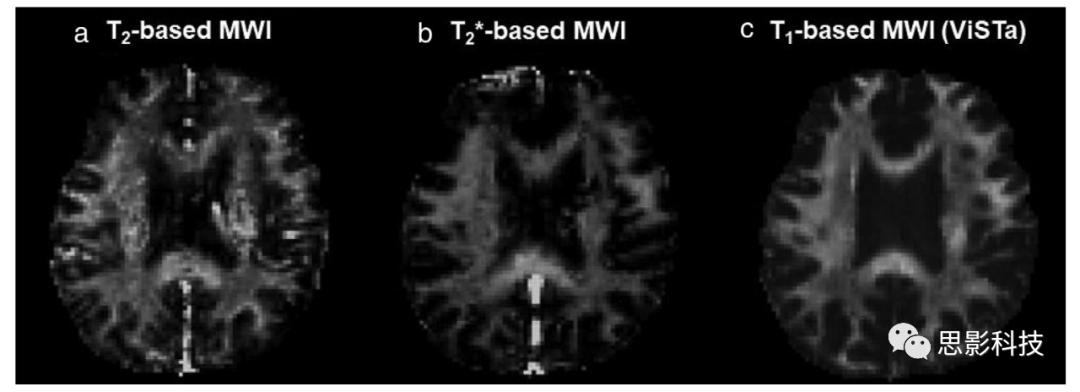

基于T2的髓鞘水成像:这是MWI的传统技术,利用髓鞘水的短T2特性来将髓鞘水信号与AEW信号序列分开。该方法获得了一个T2衰减曲线,该曲线既有髓鞘水又有AEW信号的贡献,并生成一个T2分布,区分每个T2隔室的信号贡献(图2a)。对于数据采集,常用的是多回波自旋回波序列及其变种,如多回波梯度和自旋回波(GRASE)读出序列和一个T2准备序列。为了从多回波数据中生成T2分布,已经应用了带有刺激回波校正的多指数函数拟合。但是,指数函数在数学上不是正交的,因此不能轻易区分。因此,拟合对噪声敏感。为了提高拟合的可靠性,常用的是Tikhonov正则化,它强制最小能量并生成平滑的T2分布(请参见补充图S1,了解正则化因子在T2分布和MWI( 髓鞘水成像)中的效果)。生成T2分布后,计算髓鞘水分数(MWF),这是髓鞘水信号与总水信号之比(图1c)作为该方法的定量测量。还建议T2的几何均值作为一个有用的参数。

已经证明,基于T2的MWI(髓鞘水成像)与髓鞘组织学高度相关,并已在从神经退行性疾病到神经可塑性的许多研究中应用,证明了该方法的实用性。此外,已经报道,感兴趣区域(ROI)(例如,genu)水平的重复性对于会话(session)内、会话间、多中心和多供应商研究都很高。然而,由于数据拟合过程的条件不良,MWF(髓鞘水分数)图像嘈杂(图3a),并且体素级的重复性不高。此外,分隔髓鞘水和AEW的阈值(例如,40毫秒)和正则化因子会影响MWF(补充图S1)。隔室水交换(即,髓鞘水和AEW之间的水交换)也可能导致MWF低估。为多回波自旋回波生成重复使用的再聚焦RF使数据采集效率低于基于T2*的MWI。RF的大量使用可能会在超高场MRI中达到特定吸收率(SAR)的限制。

基于T2*的髓鞘水成像:与T2技术类似,最初提出的基于T2*的MWI是为了利用水分子隔室之间的T2*差异(表1 43)。然而,随着对髓鞘磁化率的最近了解,基于T2的MWI的信号模型已经被修订,以包括不仅是T2*衰减,还有髓鞘水的信号特性中描述的频率偏移(参见问题与答案3,共振频率偏移)。为了包括频率偏移,复值MR图像的幅度和相位都被用于数据处理。这种频率偏移的结合有助于改进MWF的估计,特别是当白质纤维垂直于B0时。

基于T2*的髓鞘水成像(MWI)的数据采集使用多回波梯度回波(GRE)序列来获取信号衰减和频率偏移。这种序列与其T2对应物相比既有优点也有缺点。一些重要的优点包括高数据采集效率和低SAR,因为不需要反相射频脉冲。例如,在使用GRASE读出和3毫秒读出持续时间的基于T2*的MWI中,最小回波间隔是10毫秒,而在相同读出持续时间的基于T2*的MWI中,最小回波间隔只有3.1毫秒。换句话说,基于T2*-的MWI的数据采集效率高出三倍以上。此外,如最近所示,基于T2*的MWI的低SAR在7T时尤其有用。然而,GRE(多回波梯度回波)对B0不均匀性和稳定性的高敏感性在基于T2*的MWI中引入了一个主要的挑战。为了减轻B0引起的退化,已经提出了补偿技术。另一个重要的考虑是,髓鞘水的短T1在使用短TR和大翻转角时可能会导致MWF(髓鞘水分数)的高估。为了避免这种高估,需要仔细选择采集序列和参数(即,建议使用长TR的2D多切片成像)。

基于T1的髓鞘水成像:获取髓鞘水信号的另一种方法是利用髓鞘水的短T1特性(参见问题和答案3,纵向弛豫)。可以获得多个反转恢复数据来生成T1弛豫图。然而,由于T1的恢复速度慢,这种方法需要较长的扫描时间。作为一种替代方法,已经提出了使用反转RF抑制非髓鞘水信号以获取仅髓鞘水信号的想法。这个想法在概念上与FLAIR类似,FLAIR抑制CSF信号,并基于CSF和组织之间的T1差异生成仅组织信号。由于白质T1具有区域变异以及受试者之间的变异,为了增加抑制的稳健性,抑制不是单一的T1而是一系列的T1是很重要的。为此,为3T人类MRI设计了一个精心计时的双反转RF序列,该序列几乎去除了所有AEW、灰质和CSF信号。在抑制后,已经显示剩余的信号主要是髓鞘水信号(>95%),证明可以在没有任何数据处理的情况下获得髓鞘水图像。这种新方法的信号特性,被称为ViSTa-MWI,已经被证明具有与髓鞘水匹配的T2*衰减,频率移位和MTR。

为了有效地获取3D体积(volume),ViSTa-MWI读出使用3D分段回波平面成像实现,覆盖整个大脑,在8分钟内得到2毫米等距体素(表2)。因为这种方法不需要任何条件不良的数据拟合,与传统方法相比,ViSTa-MWI提供了显著改善的图像质量和重复性(图3c)。为了量化髓鞘水信号,已经提出使用相同读出的质子密度加权图像进行图像标准化。然而,这种标准化需要标称值校正,这可能是错误的来源(补充图S3)。此外,双反转RF不仅抑制AEW信号,而且部分抑制髓鞘水信号。由于抑制时间长,这种部分抑制以及隔室水交换可能很大,导致MWF(髓鞘水分数)被低估。因此,ViSTa的测量MWF大约是传统MWI中MWF值的三分之一。由于这种差异,ViSTa-MWI的MWF被称为表观MWF,以避免混淆。当需要髓鞘水的绝对量化时(例如,g-ratio),这种限制可能是潜在的重要性。尽管如此,ViSTa-MWI的表观MWF可以用于受试者内或受试者间比较以及横断面和纵向研究。该方法已成功应用于MS、神经脊髓炎和创伤性脑损伤研究。

图3:基于T2、T2*和T1的MWI的样本MWF图。所有数据都是以2毫米等距体素大小(名义分辨率)获得的。